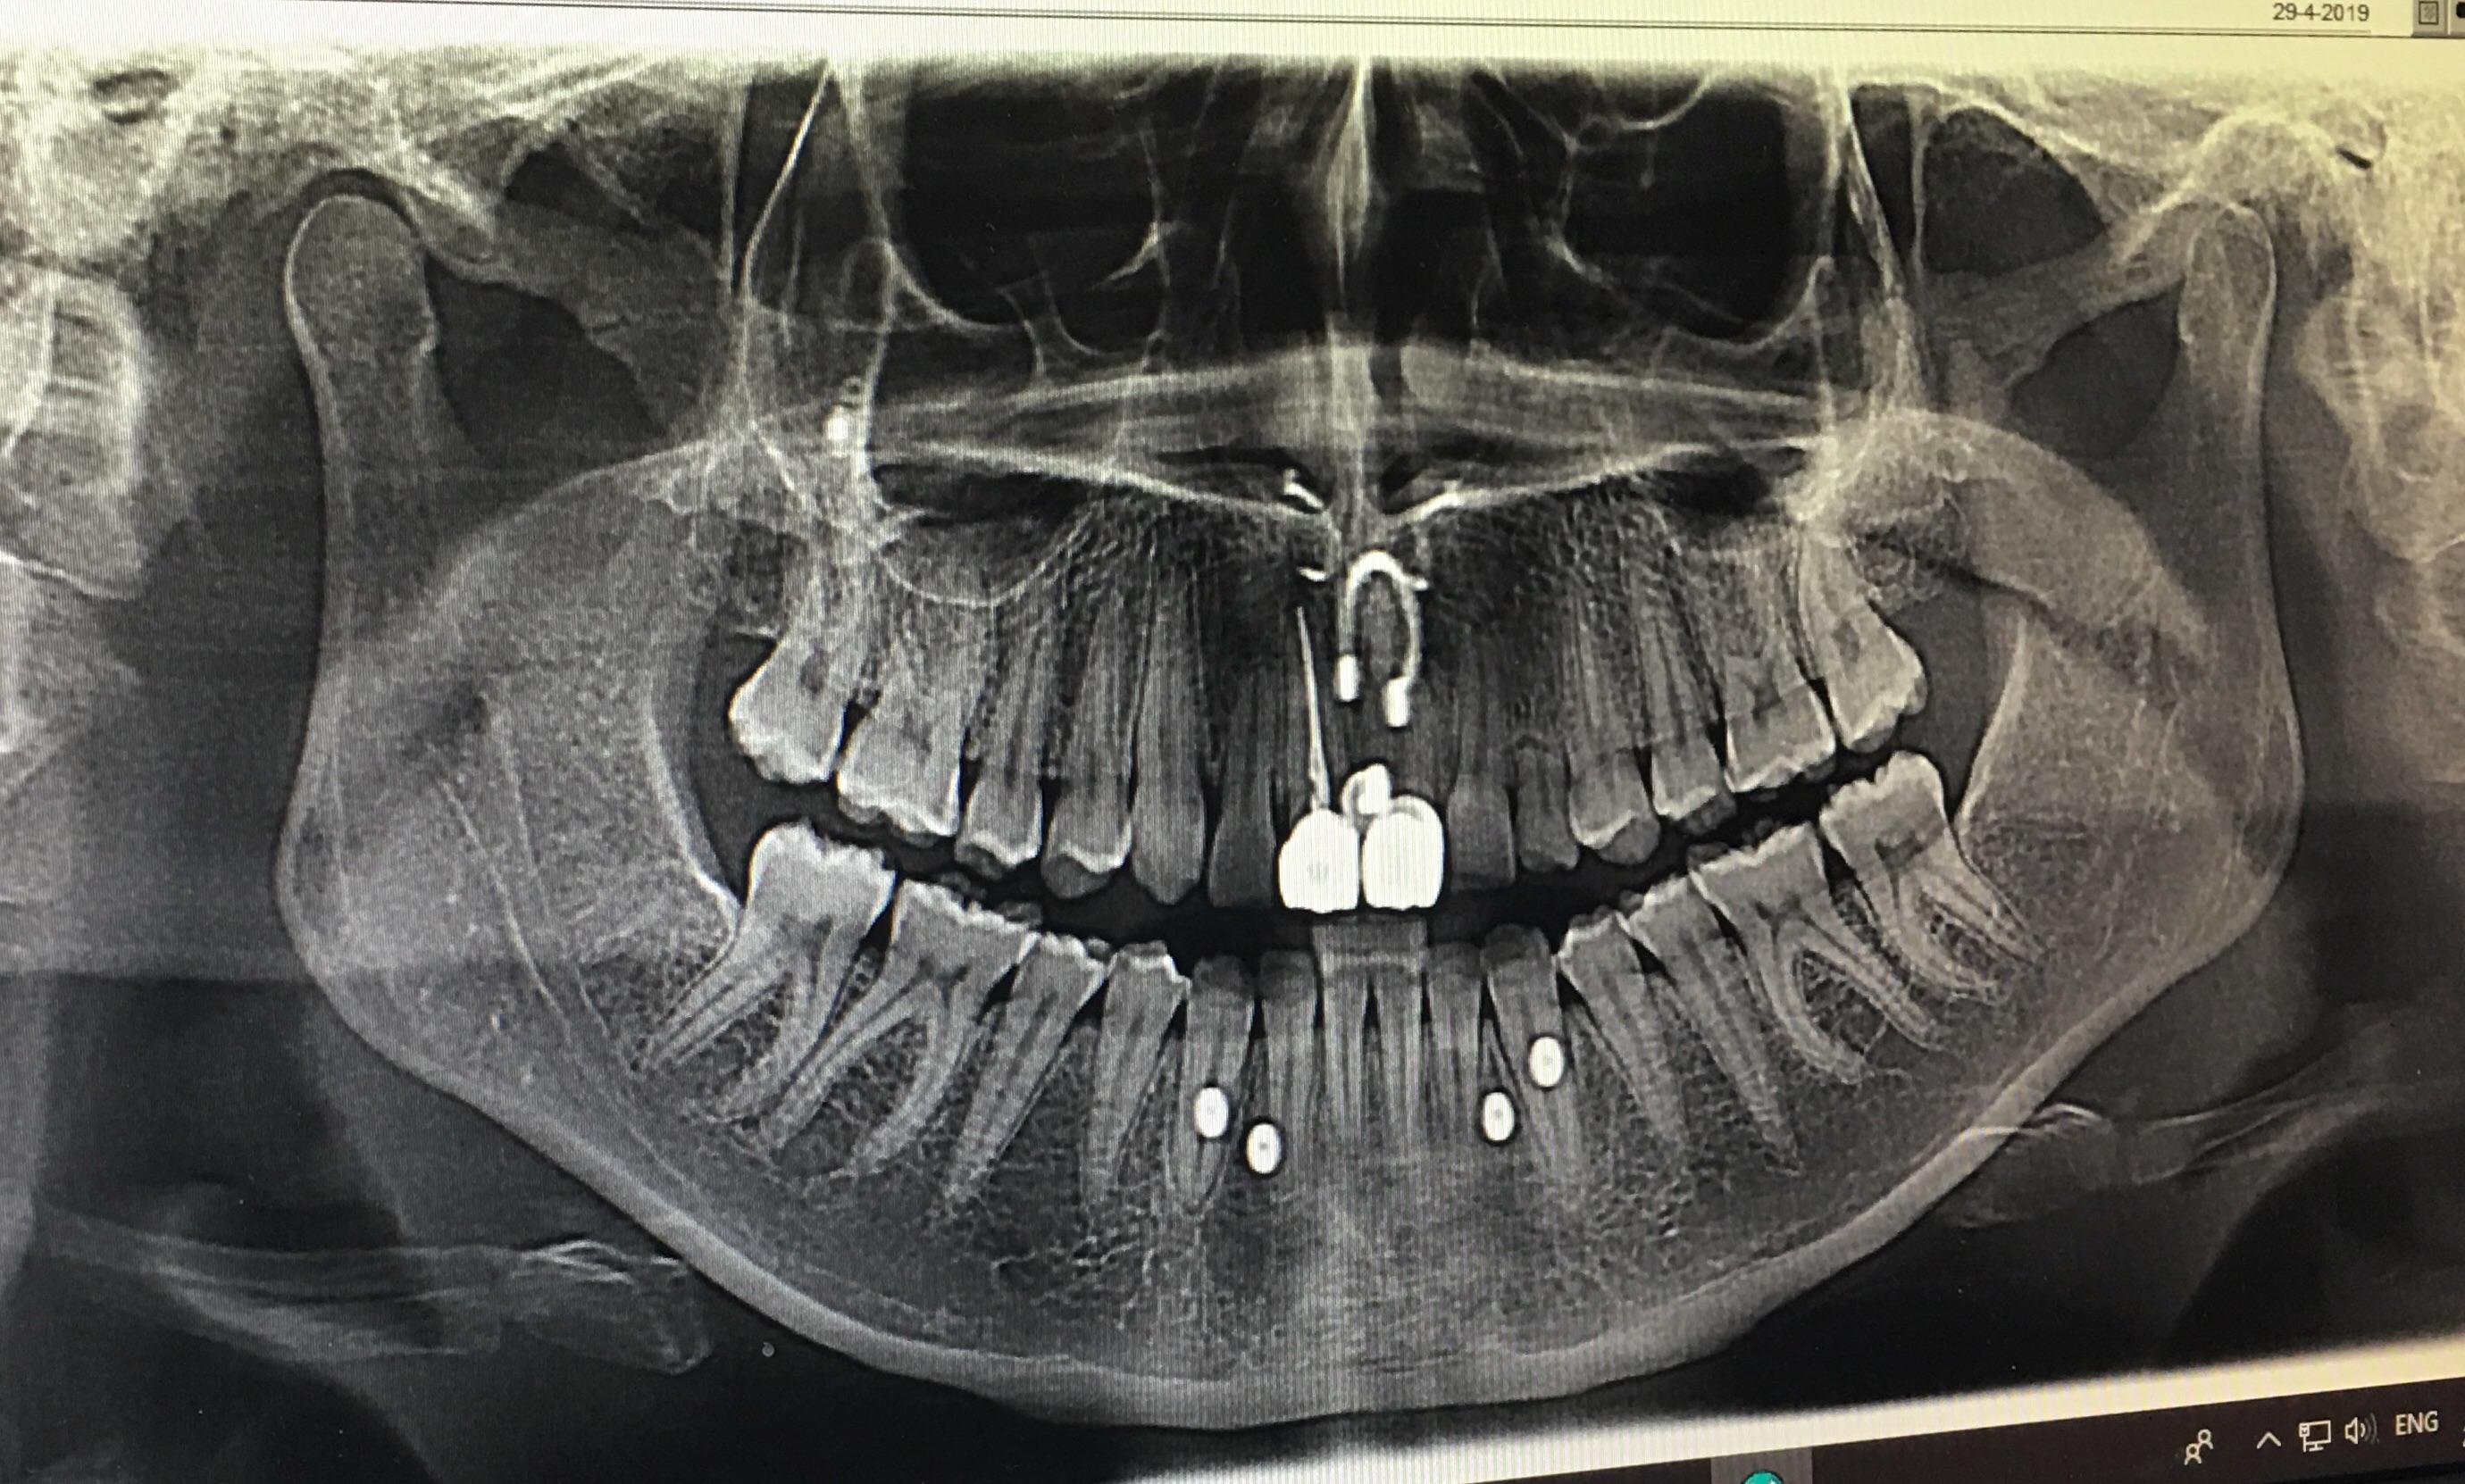

Dental X Rays And Piercings . This image depicts the entire upper. Panoramic radiography is a commonly used imaging technique in radiology and may be a component of your radiologic examination. But what is a dental piercing? By avoiding production of these artefacts when possible, we can reduce radiation exposure to patients while obtaining the most diagnostically. What are dental gems and piercing? Tongue piercing results in dental and. Before deciding on an oral piercing, consider discussing it with your dentist beforehand. What are its effects on oral health, and are there any risks?

Panoramic radiography is a commonly used imaging technique in radiology and may be a component of your radiologic examination. But what is a dental piercing? What are its effects on oral health, and are there any risks? Tongue piercing results in dental and. Before deciding on an oral piercing, consider discussing it with your dentist beforehand. This image depicts the entire upper. By avoiding production of these artefacts when possible, we can reduce radiation exposure to patients while obtaining the most diagnostically. What are dental gems and piercing?

Dental X Rays And Piercings Panoramic radiography is a commonly used imaging technique in radiology and may be a component of your radiologic examination. Before deciding on an oral piercing, consider discussing it with your dentist beforehand. What are dental gems and piercing? But what is a dental piercing? Tongue piercing results in dental and. By avoiding production of these artefacts when possible, we can reduce radiation exposure to patients while obtaining the most diagnostically. Panoramic radiography is a commonly used imaging technique in radiology and may be a component of your radiologic examination. What are its effects on oral health, and are there any risks? This image depicts the entire upper.